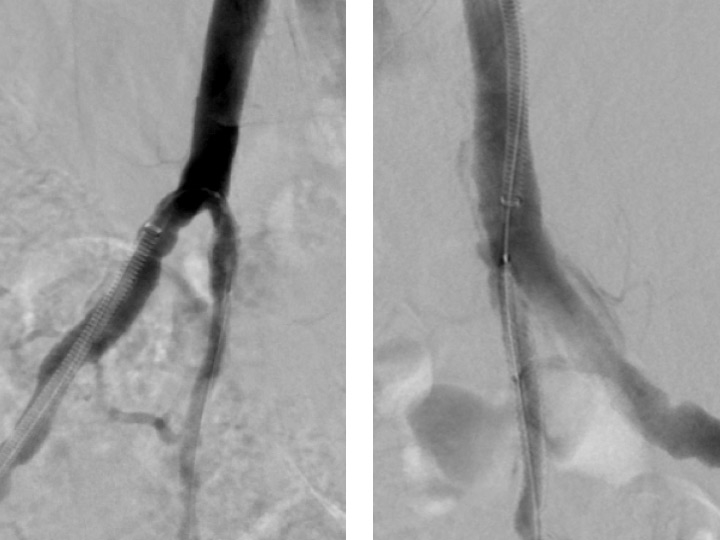

Figure 4

Angiographic result after bilateral placement of drug eluting stents.

Endovascular therapy for obstructions of the common iliac and hypogastric arteries has traditionally been performed for many years. Figures 3 and 4 show angiograms of the pelvic arteries of a 62-year-old architect with erectile dysfunction. He had undergone aorto-coronary bypass grafting 3 years previously and, based on duplex ultrasound, an arterial inflow obstruction had been diagnosed. On intra-arterial angiography, a high-grade obstruction of both hypogastric arteries was diagnosed (fig. 3), both of which have been stented using drug-eluting stents (fig. 4). Erectile dysfunction in this patient was significantly improved during follow-up.